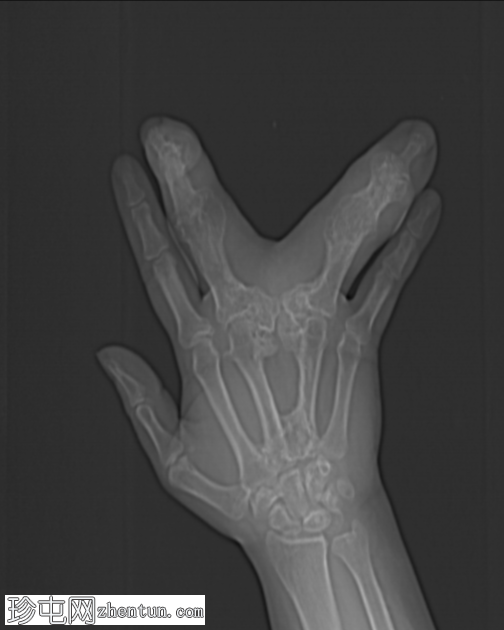

无名指和中指明显增大。患者掌骨和指骨骨质增生肥大,并伴有周围皮下脂肪过度增生。

CT 扫描显示骨质过度生长和肥大、皮下脂肪过度生长以及神经纤维脂肪瘤性错构瘤。